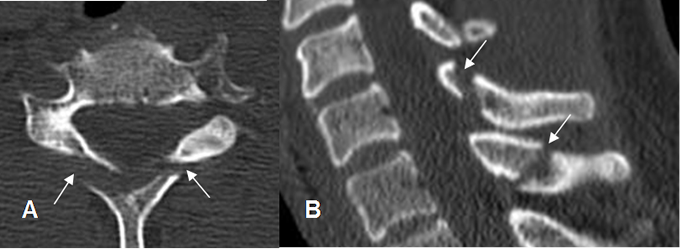

Fig 161. Fractura estable.

A: TAC axial y B: TAC reconstrucción sagital. Fractura no desplazada de ambas láminas vertebrales, por lesión estable.